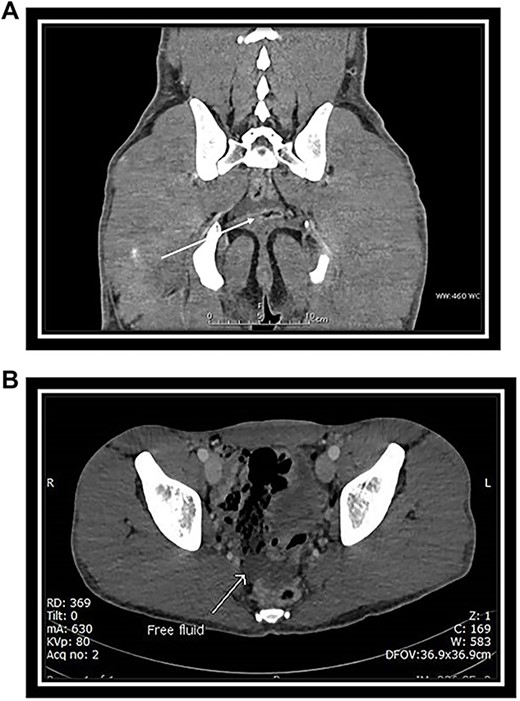

Abdominal CT with intravenous (IV) contrast (Fig. 2A and B) revealed:

(A) Coronal CT scan section: arrow indicates free fluid in the Douglas pouch. (B) Axial CT scan section: arrow indicates free fluid in the Douglas pouch.

No solid abdominal organ injuries.

Mild free fluid was noted in the pelvis.

No abnormal bowel enhancement or bowel dilatation.

No free air in the abdomen.

The bones were intact.